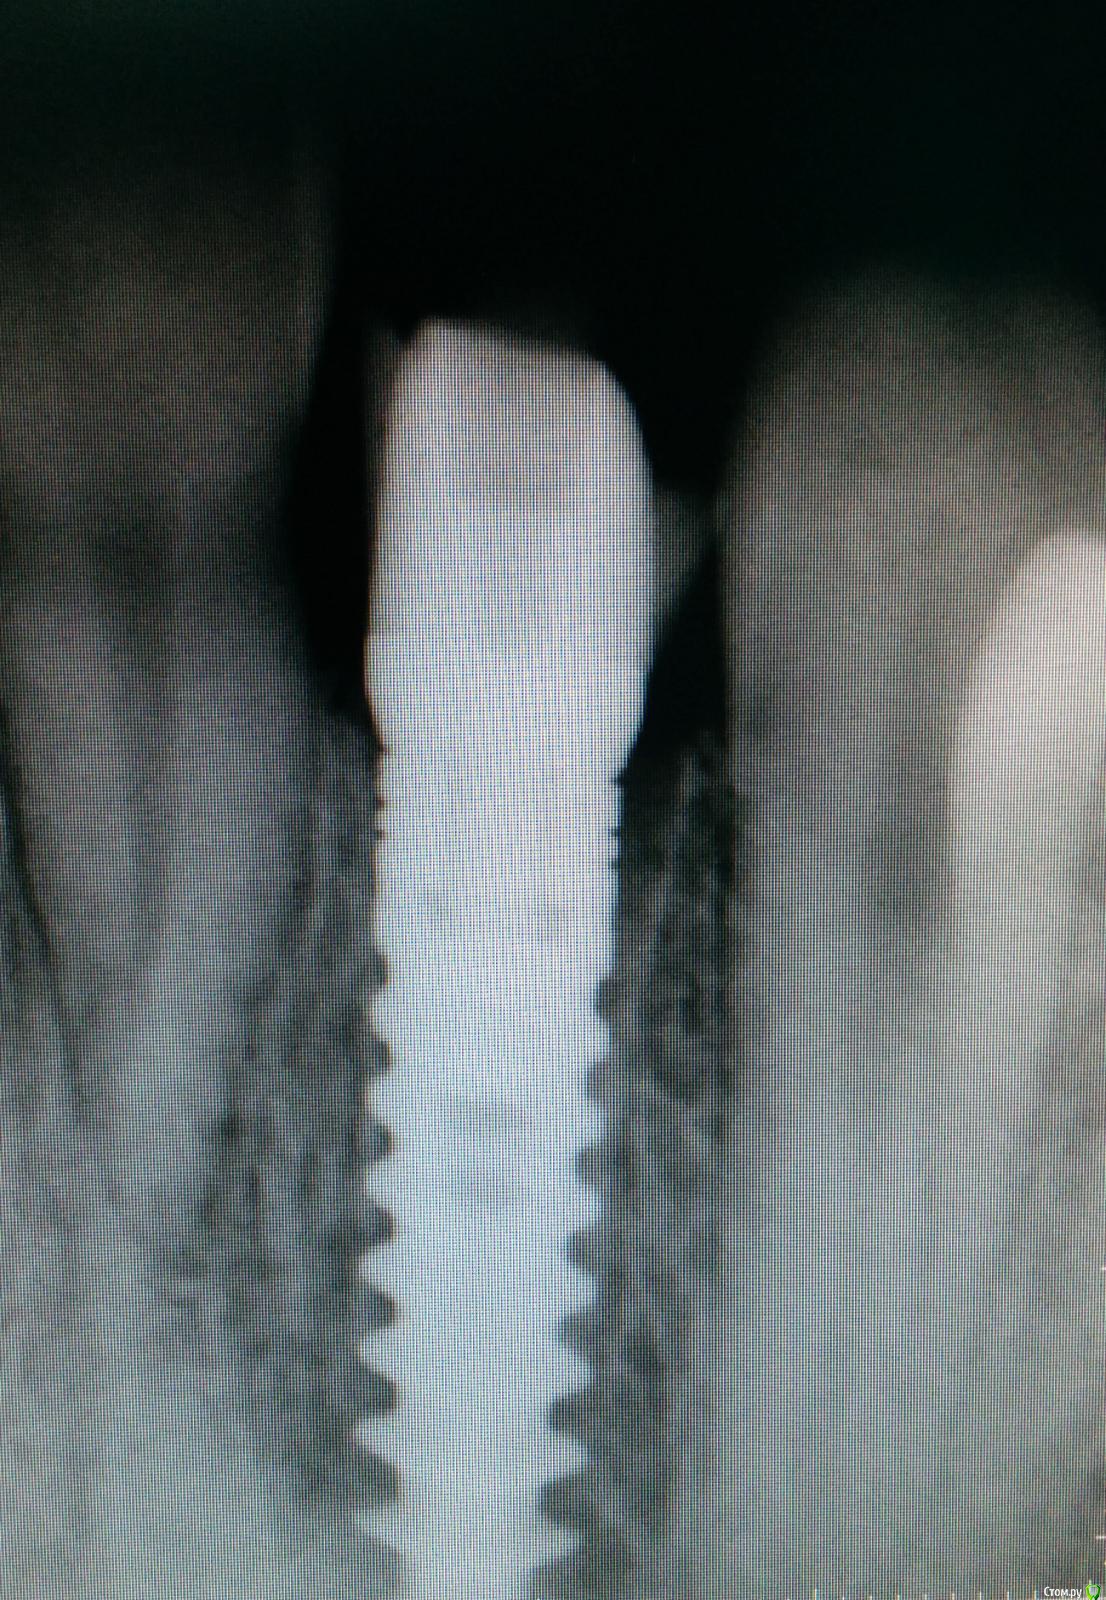

an_ver Опубликовано 2 апреля, 2015 Поделиться Опубликовано 2 апреля, 2015 SPI? В лунку что нибудь кидали во время установки? Ссылка на комментарий

Lolopop Опубликовано 3 апреля, 2015 Поделиться Опубликовано 3 апреля, 2015 альфабио?)))какой торк получили? Ссылка на комментарий

АнтонТЛТ Опубликовано 4 апреля, 2015 Поделиться Опубликовано 4 апреля, 2015 Судя по фото Alpha bio SPI, торк около 40 Ссылка на комментарий

MenshikovDV Опубликовано 5 апреля, 2015 Автор Поделиться Опубликовано 5 апреля, 2015 торк намного больше 40 Ссылка на комментарий

Brigita Опубликовано 5 апреля, 2015 Поделиться Опубликовано 5 апреля, 2015 на удаленном зубе какая то железячка хвостиком торчит))) Ссылка на комментарий

Saymon Опубликовано 6 апреля, 2015 Поделиться Опубликовано 6 апреля, 2015 на удаленном зубе какая то железячка хвостиком торчит)))Все нормально. Это WI-FI антенна. 4 Ссылка на комментарий

MenshikovDV Опубликовано 7 апреля, 2015 Автор Поделиться Опубликовано 7 апреля, 2015 ИНСТРУМЕНТ сломан в канале )) Ссылка на комментарий